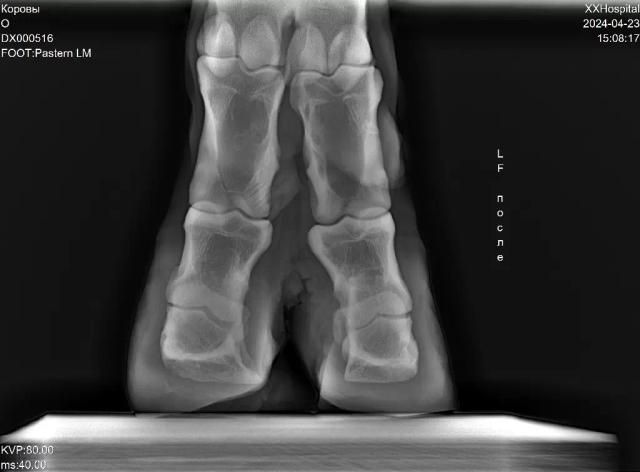

Рентген копытца до обрезки и после нее